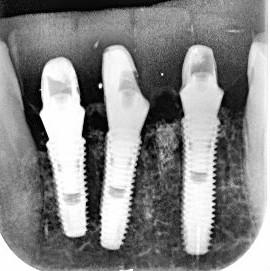

Pacjent z długą historią leczenia implantologicznego. Pierwsze implanty w pozycjach 23, 24 miał wkręcane w Warszawie przed 25 laty. Implant w pozycji górnego prawego kła ma agresywny gwint, ponieważ bezpośrednio po implantacji był obciążony (immediate loading) tymczasowym atachmentem ball abutmentv do stabilizacji tymczasowej protezy ruchomej. Kość szczęki regenerowana i odbudowywana etapami w całym górnym prawym kwadrancie. Pacjent planuje uzupełnić brakujące zęby 25, 26.